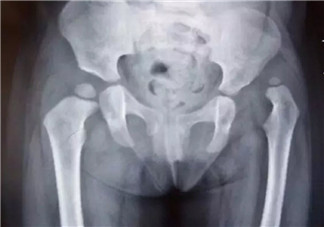

一歲前寶寶發育脊椎段是頸椎、胸椎和腰椎,所以俗話說寶寶三月抬頭、六月坐,九月爬行,周年學走;要學好這些動作,脊椎發育很重要,學習有快有慢,發育不全急著坐會傷害脊椎,對日后影響更嚴重喔!對于很多的家長不知道1歲前的寶寶的脊椎的發展,下面八寶網的小編為大家分享1歲寶寶的脊椎發展的正確的觀念,如何幫助寶寶脊椎發育。

一歲前是脊椎發育的黃金關鍵期,而這個階段寶寶的睡眠時間是屬于比較長的;骨骼肌肉的發育都尚未成熟,也還未定型,可塑性非常大,因此要特別留意睡眠的姿勢。

寶寶要能站的基礎在于肌肉和骨骼的發育穩定了,還有脊柱發展到了腰椎的部分,否則地心引力的關系,加上上半身比較重,會讓他的身體想往下沉,反而影響他的站姿。

4、腿型容易變形

脊椎發育時期提早學站學走很容易出現O型腿和X腿,骨骼柔軟時做這些動作,等到成人骨骼變硬,才來修正就會變得很辛苦,不要早站早坐,多翻身多爬行,對智力發育和走路才有真正幫助。

5、脊椎承受壓力